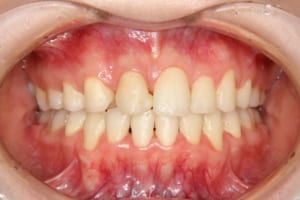

治療前

治療後

年齢・性別 19才 女性

主訴 下の歯の凸凹

上の前歯が出ているのが気になる

その他/備考 上顎右側中切歯および側切歯が、埋伏していた犬歯によって歯根吸収していました。